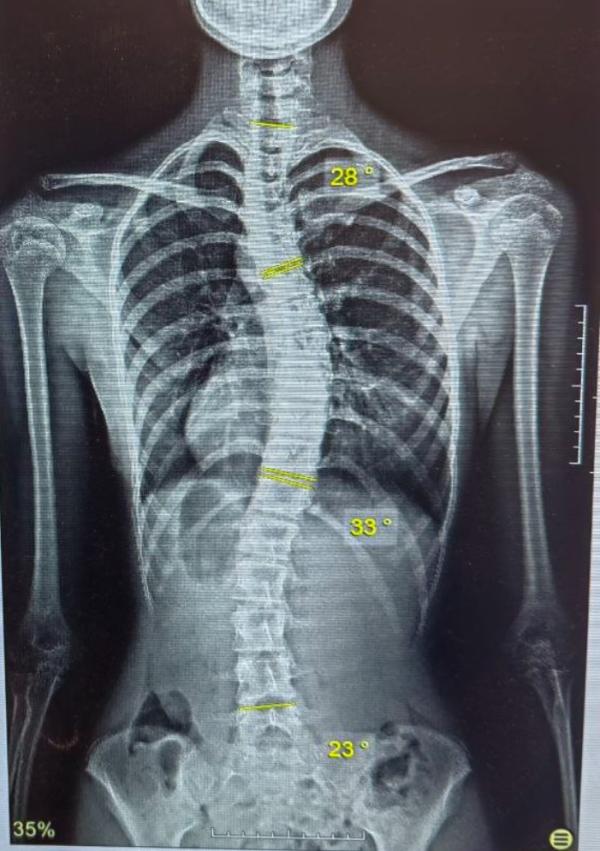

Сегодня пришла, провели тестирование, измерили сколиометрию и мне нравится что тело не ухудшило ротацию позвоночника и размер сколиоза.

Наконец-то четко и почти идеально сделали позу самокоррекции сидя. На коллаже фото спустя месяц перерыва: видно как дуга стала выше и ближе к центру тела.

Эта так работает подбор комплекса специальной гимнастики Шрот и Сеас. Даю комплексно+силовой тренинг для формирования мышечного корсета. Также эта пациентка носит регулярно корсет Шено.